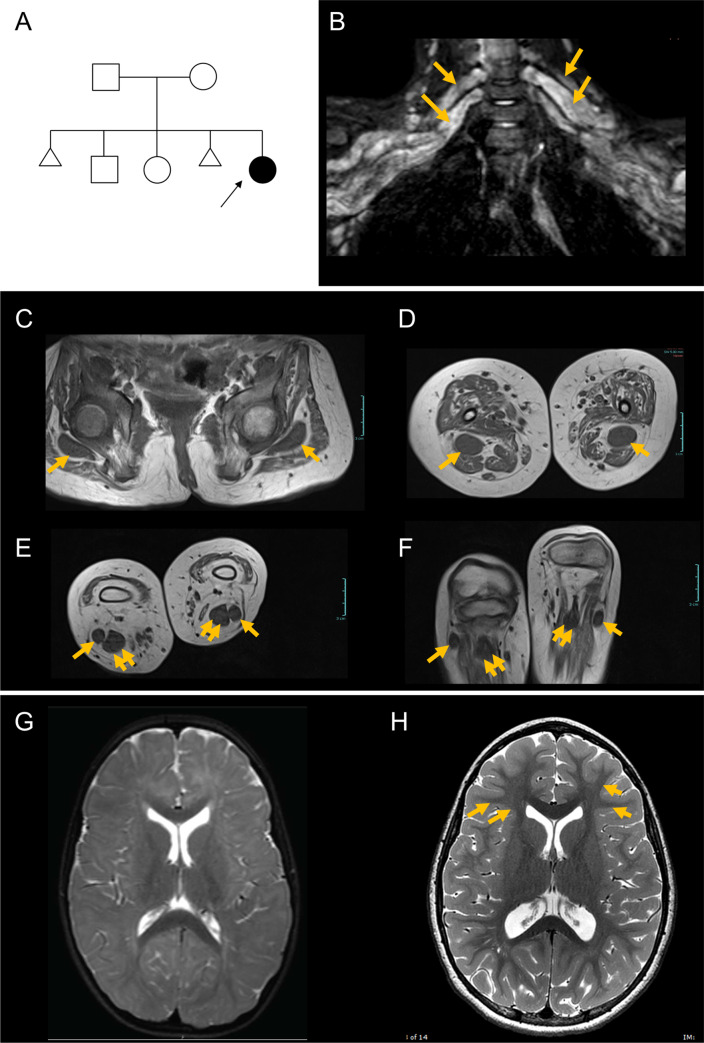

Fig 1 Proband has myelination defects and greatly enlarged nerves.

(A) Pedigree of the family; arrow points to the proband; triangular shapes indicate instances of spontaneous abortion. (B-F) MRI of upper and lower extremities demonstrates enlarged nerves. (B) Image showing greatly enlarged brachial plexus. Arrows indicate the thick peripheral nerves. (C) Sciatic nerve at the level of the femoral head (arrows). (D) Sciatic nerve at the level of the mid-thigh (arrows). (E) Posterior tibial (double arrows) and peroneal (single arrows) nerves at their origins. (F) Posterior tibial (double arrows) and peroneal (single arrows) nerves at the level of the fibular head. Scale bars, 3 cm. (G) Representative brain MRI (axial, T2-weighted) showing poor delineation of white and gray matter, indicating reduced myelination, when compared to age-matched control (H). Note the delineation of white and gray matter in control (arrows) that is not seen in the patient.